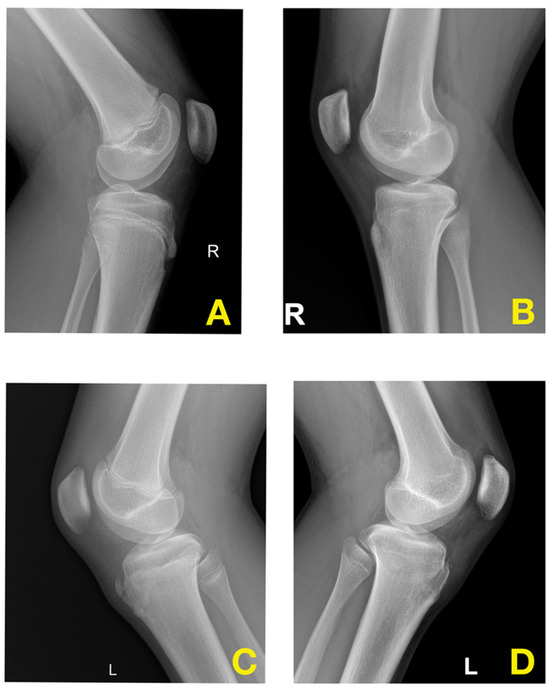

3.4. Radiological Evaluation